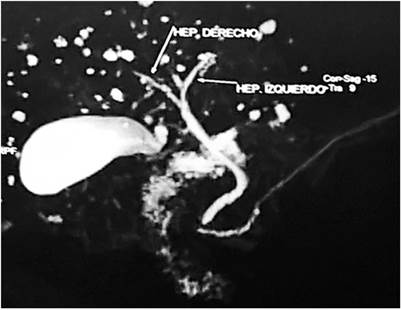

Durante la hospitalización, se realizó una colangiorresonancia contrastada, en la cual se evidenciaron múltiples dilataciones saculares en las vías biliares intrahepáticas: EC (tipo V, según la clasificación de Todani) (Figura 1).